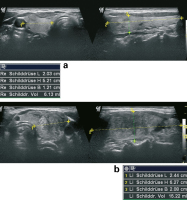

Abbildung 2a-b: Dieselbe Patientin vier Monate später. 2a: Mäßige Volumsabnahme im rechten Lappen, sonografisches Muster wie bei der Erstvorstellung (links Querschnitt, rechts Längsschnitt). 2b: Der linke Lappen nun deutlich kleiner als bei der Erstvorstellung. Deutliche Normalisierung des Parenchymmusters im Ultraschall.